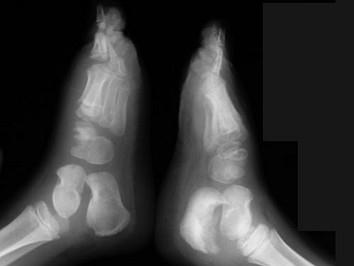

女,5岁,左踝疼痛,请结合图像,选出最可能的诊断 ( )A、风湿性关节炎B、痛风C、退行性骨关节病D、神经性关节病E、创伤性关节炎

问题 女,5岁,左踝疼痛,请结合图像,选出最可能的诊断 ( )

选项 A、风湿性关节炎 B、痛风 C、退行性骨关节病 D、神经性关节病 E、创伤性关节炎

答案 D